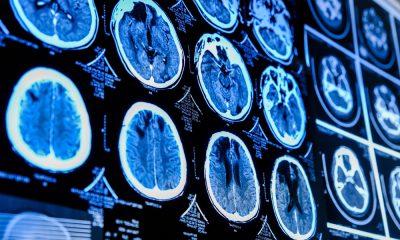

Ageing alters the brain’s shape in measurable ways that could provide early warning signs of dementia, potentially years before symptoms...

According to a new study, people who have no dementia risk factors, including the likes of diabetes, hearing loss and smoking, have brain health similar to...

Diagnosing Alzheimer’s disease can be a relatively slow process involving lengthy in-person neuropsychological exams, transcriptions by clinicians, reviews and detailed analysis. Researchers at Boston University, however, have developed a...

A new study suggests that a high-fat diet could be implicated in severe brain damage. An international study has uncovered a link between a high-fat diet and...